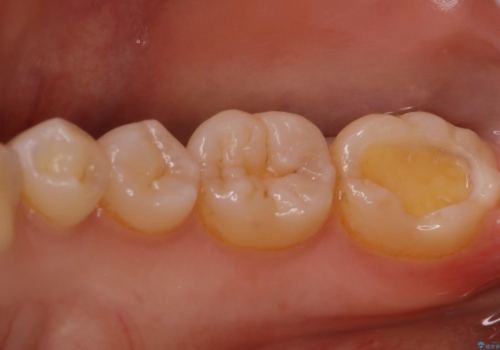

- 昔保険で治療した詰め物の形をずっと気にされていた患者様です。また下の歯なのでお口を開けると見えてしまうことを気にされていました。白く丈夫な被せ物を奥歯に入れたいと希望されたため、セラミックインレーにて治療いたしました。

保険でよく使用されるコンポジットレジンが詰めてありました。時間が経つと劣化しやすい材質なため全て取り除き、形を整えてセラミックインレーを被せました。キレイな歯の形を手に入れることができ、ご満足いただけました。